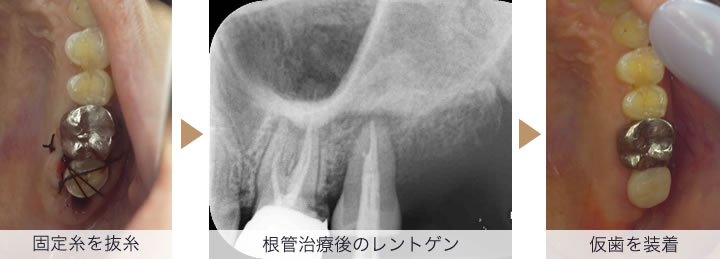

残せない歯を抜歯、さらに親知らずを抜歯し保存します。すぐに抜歯した親知らずを残せない歯を抜歯した部分に移植します

一週間後に抜糸し移植歯がある程度固定され歯肉が治癒してきたら、根管治療をします。その後、4か月ほど移植歯が骨とくっつき安定するまで待ち仮歯を入れ様子をみます。

移植した歯が安定したので、被せ物を装着し、治療完了となります。

治療後のレントゲン写真にて、移植歯の周りに骨ができており、移植が問題なく成功していることがわかります。